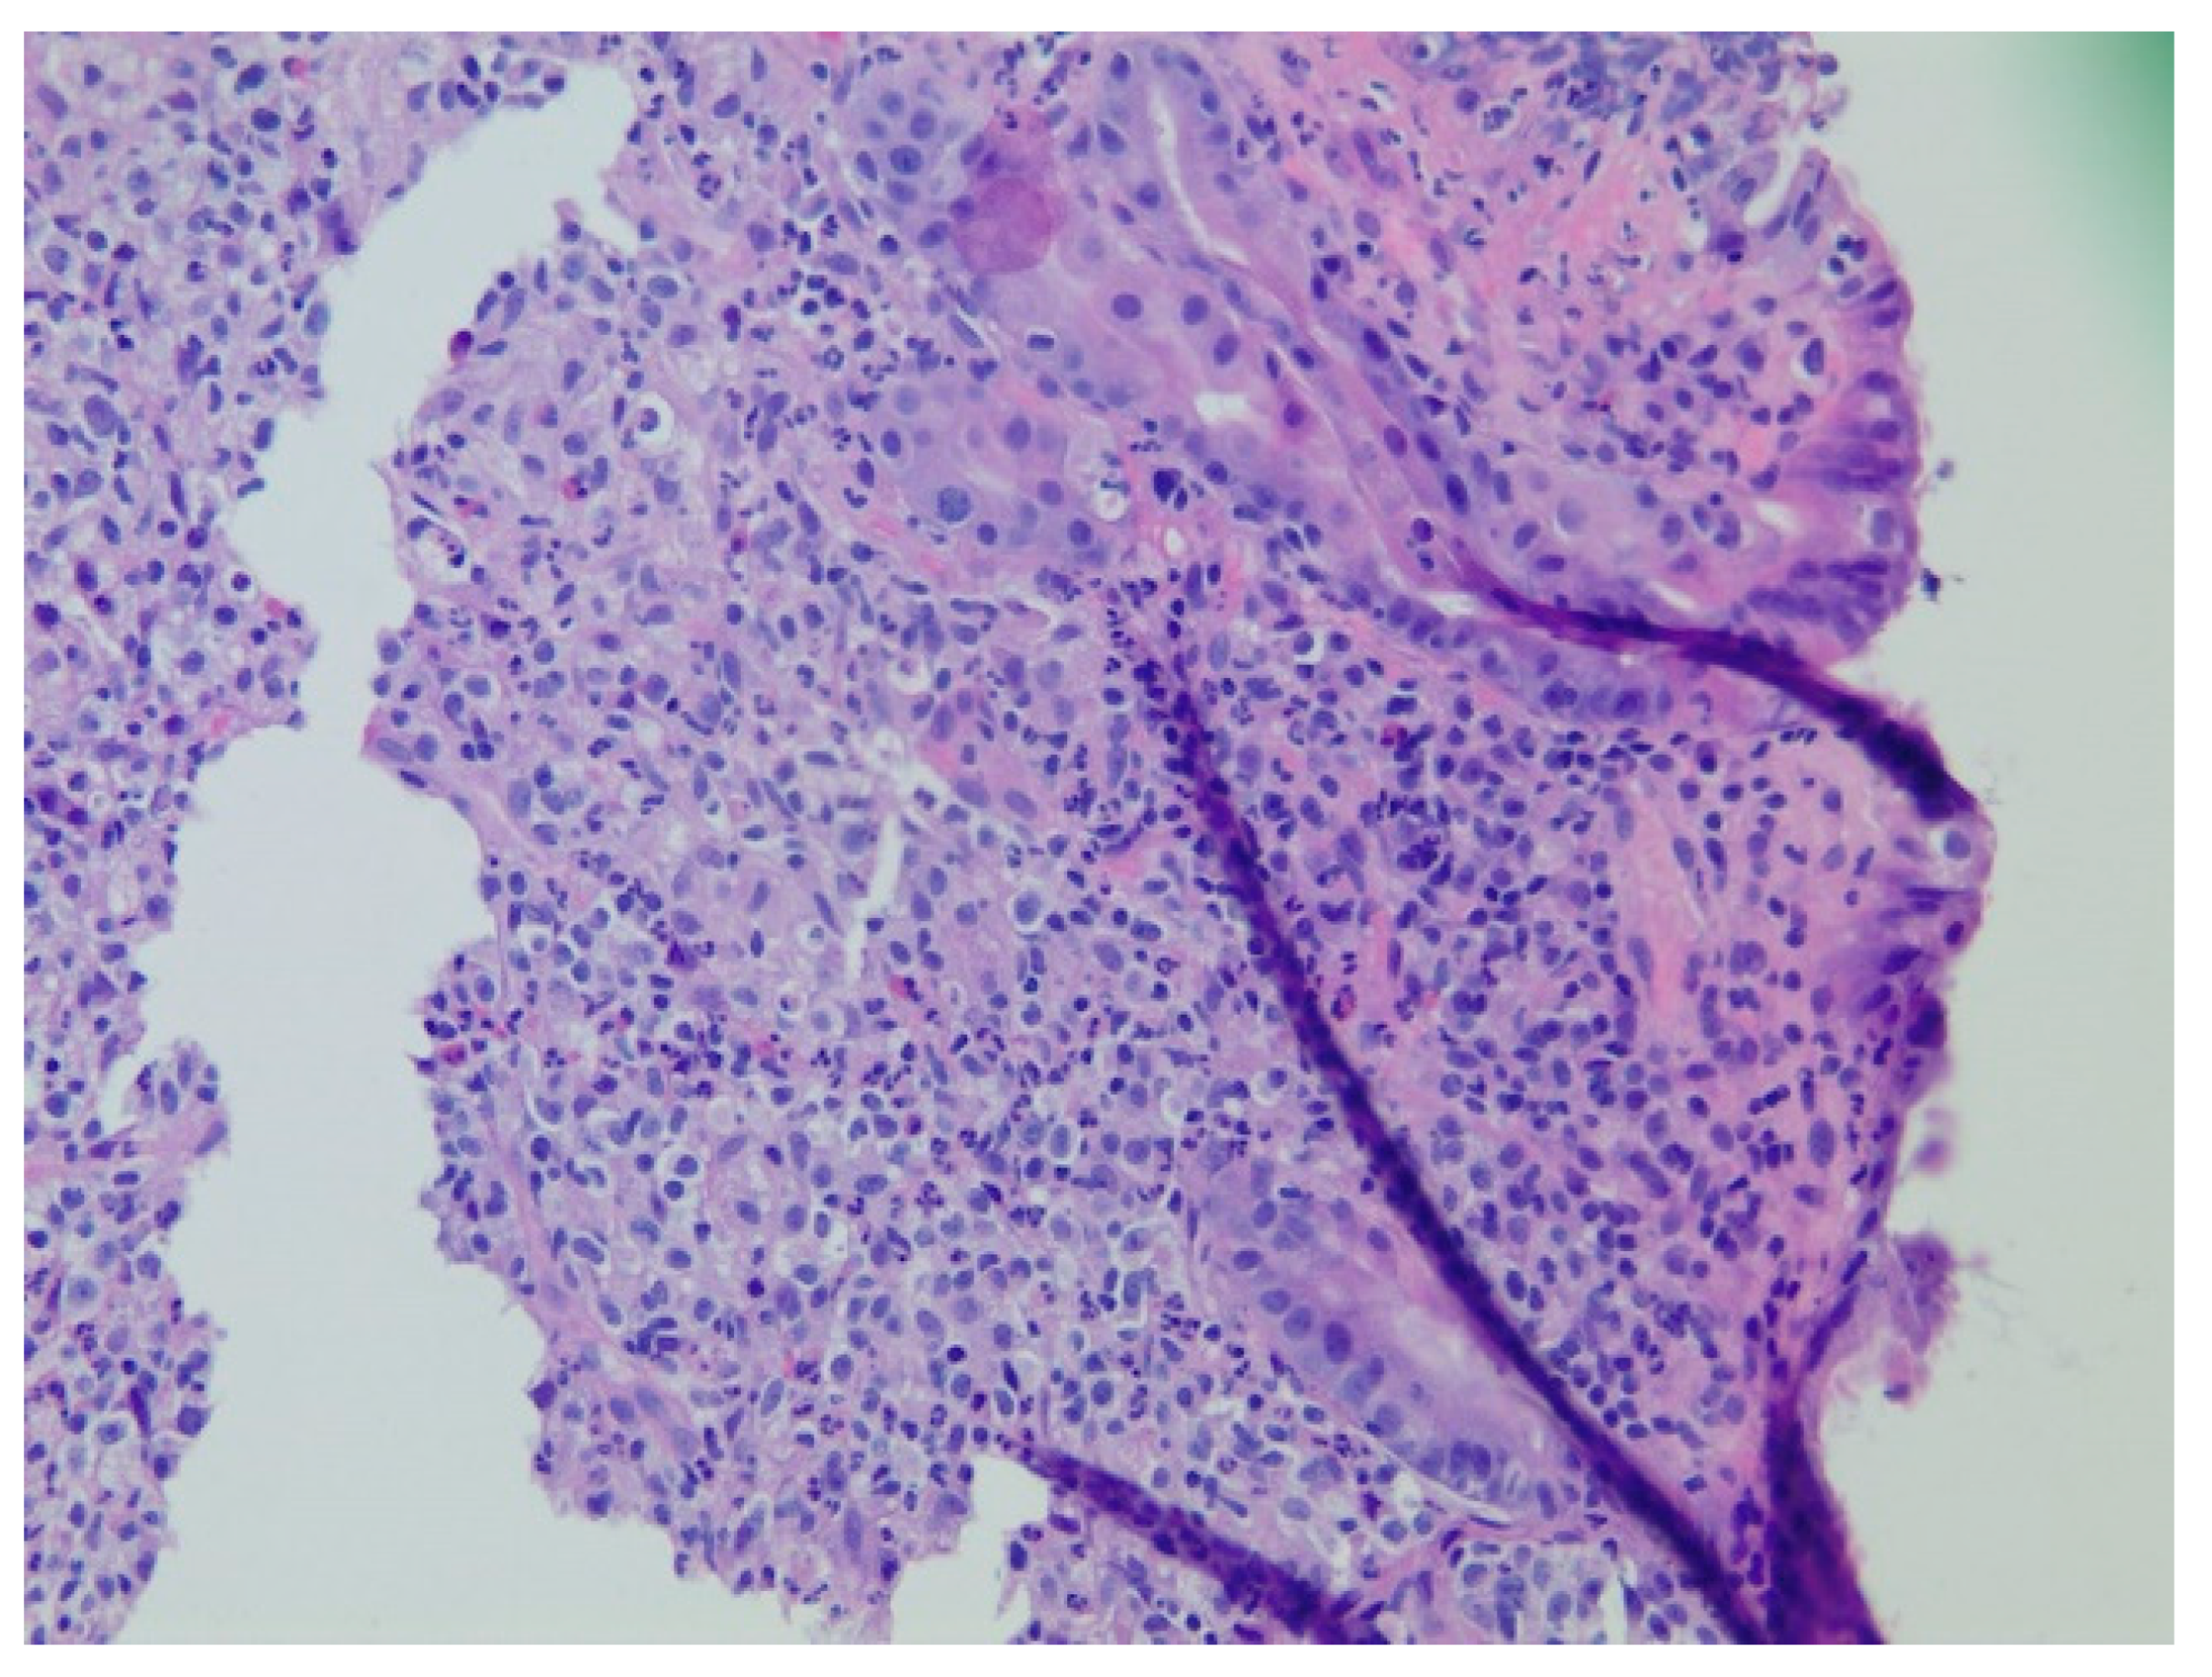

| 1 | F | 66 | Skin | Fundus, cardia, and body | Polypoid lesions with superficial ulcers | Esophagus, duodenum, mediastinum, cervical soft tissue, pancreas | Metastatic malignant melanoma | Radiotherapy and immunotherapy | Comfort care and death 5 days after EGD diagnosis of metastasis |

| 2 | M | 84 | Lymphoid | Fundus and cardia | Ulcerated and necrotic mass | Liver, urinary bladder | Diffuse large B-cell lymphoma | None | Death in 2 months after EGD diagnosis of metastasis |

| 3 | F | 35 | Lung | Fundus | Fungating mass | Esophagus, mediastinum | Large-cell neuroendocrine carcinoma | Chemotherapy-carboplatin/ etoposide | Death 1 month after EGD diagnosis of metastasis |

| 4 | F | 73 | Kidney | Fundus and body | Multiple large friable masses | Liver and lungs | Clear cell renal carcinoma | Nephrectomy, chemotherapy, immunotherapy (Axitinib) | Death 10 days after EGD diagnosis of metastasis |

| 5 | M | 76 | Lung | Body | Cratered ulcers | Liver, bone and adrenals | Small cell carcinoma (poorly differentiated neuroendocrine Ca) | None | Death 7 days after EGD diagnosis of metastasis |

| 6 | M | 61 | Lymphoid | Unknown | Clean based ulcer | None | Marginal zone lymphoma | Rituximab, Zanubrutinib, umbrasilib. OCHOP regimen currently | Progressive disease per latest scans despite therapy |